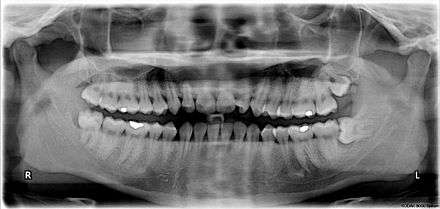

A wisdom tooth or third molar is one of the three molars per quadrant of the human dentition. It is the most posterior of the three. Wisdom teeth generally erupt between the ages of 17 and 25.[1] Most adults have four wisdom teeth, one in each of the four quadrants, but it is possible to have fewer or more, in which case the extras are called supernumerary teeth. Wisdom teeth commonly affect other teeth as they develop, becoming impacted. They are often extracted when this occurs.

Wisdom teeth (often notated clinically as M3 for third molar) have long been identified as a source of problems and continue to be the most commonly impacted teeth in the human mouth. The oldest known impacted wisdom tooth belonged to a European woman of the Magdalenian period (18,000–10,000 BCE).[5] A lack of room to allow the teeth to erupt results in a risk of periodontal disease and dental cavities that increases with age.[6] Less than 2% of adults age 65 years or older maintain the teeth without cavities or periodontal disease and 13% maintain unimpacted wisdom teeth without cavities or periodontal disease.[7]